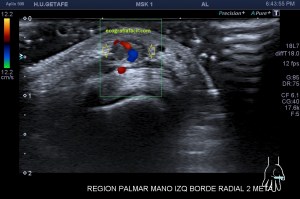

El paciente del caso que te expongo hoy como primer post del 2021 es un paciente de uno 40 años que nota desde hace un año un pequeño bultoma en la palma de la mano, en la región flexora en el eje largo del 2 dedo, a la altura de la articulación metacarpofalángica, ligeramente radial, viene referido del traumatólogo.

En mi interrogatorio habitual el paciente descarta traumatismo, no recuerda, ligero crecimiento sin dolor. Al tocar el bulto para localizarlo, lo primero que me llama la atención es que tiene pulso, muy evidente, es duro y muy pequeño, pero el pulso es muy evidente, no había coloración cutánea. El paciente ni el médico refirieron este dato superimportante (el latido) que dirigió el estudio absolutamente, como ves en la imágenes.

Escojo la sonda de ultraalta frecuencia, 18 mHz, y ajusto los parámetros para realizar un estudio con la intención de encontrar algo muy superficial, por supuesto, gran cantidad de gel, nada de presión, apoyo levemente el transductor.

Hallazgos:

1

En esta primera imagen me encuentro, primero, un estructura heterogénea, redonda, ligeramente ovalada con un centro anecoico y un halo grueso e hipoecogénico.

Lo segundo es delimitarla bien, tener bien estudiada la anatomía de referencia, imagen 2, respecto de la ecoestructura patológica y su propia ecoarquitectura. Por supuesto aplicamos el protocolo de referencia, localización, estudio, medición y vascularización que hoy ves resumido en estas 5 imágenes ya que el estudio lo enfoqué en el estudio de algo vascular.

2

La anatomía, tan importante siempre, buscando la relación, sobre todo, con el tendón al que claramente esta lesión no pertenecía ni afectaba.

3

El corte en eje largo como te indica el pictograma es muy importante, en teoría debería haber encontrado una estructura redondeada en eje corto y tubular en eje largo, como debiera corresponder a esta lesión vascular, pero los hallazgos no arrojaron dicha imagen.

Demostré el pulso en ambos ejes, pero no pude comprobar la estructura tubular en longitudinal…el motivo, el tamaño de la estructura y su gruesa pared que puedes apreciar en ambos ejes y que correspondía a una incremento de la pared del propio vaso, vaso que se encontraba parcialmente trombosado por este crecimiento de su pared, habitual en estas lesiones post traumáticas, donde el propio vaso sangra y esa sangre se colecciona alrededor el mismo.

4

Se demostró lo que ya presentía, que era la vascularización típica de un vaso, vaso que resultó ser uno de alto flujo, y  te explico…cuando estudiamos una malformación vascular por ecografía, podemos encontrarnos malformaciones de bajo flujo, las venas, de alto flujo, arterias o mixtos de ambas.

5

En la imagen 5 ves el típico aspecto de un vaso de alto flujo, lo normal, ya que tenía latido. Vas a ver dicho espectro con aspecto de picos y valles muy marcados, el sonido también es diferencial, puedes ver el doppler espectral y escucharlo. Su sonido y su aspecto es distinto del de una vena.

En este caso debí usar una muestra, flecha amarilla de la imagen 5, lo más pequeña posible, ya que el vaso lo era igual, adaptaremos esta muestra al tamaño del vaso que quieras estudiar. si la muestra no es la idónea la lectura puede ser incoherente. La muestra es el tamaño del «roi2 que hará el registro de la zona a estudio. Te enlazo arriba para que revises nociones básicas de doppler en post anteriores, también puedes consultar el índice del blog al final de este Post.

En este vídeo puedes ver como en la imagen 2D  como late la estructura, y como con el doppler color la vascularización es evidente. Puedes estudiarlo con Triplex, en el enlace a instagram ves como se estudia la lesión con una técnica de la que ya te he hablado más veces, donde puedes ver el doppler color y el espectral a la vez, eso sí, consumieno muchos recursos del equipo.

El diagnóstico final del radiólogo fue psudoaneurisma de la arteria palmar del segundo dedo.